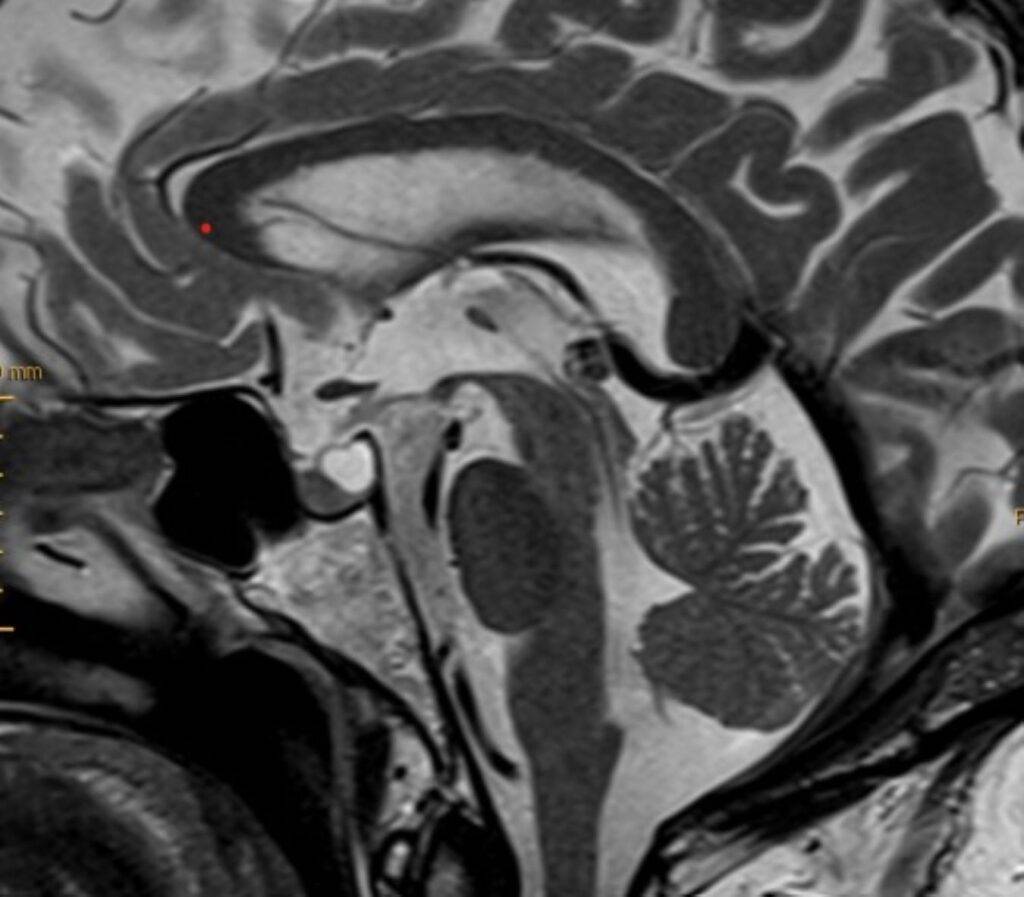

Hirntumor in der MRT

- Tumore und Zysten: Die MRT Kopf kann sowohl gutartige als auch bösartige Tumore im Gehirn erkennen. Sie kann auch bei der Identifizierung von Zysten und anderen strukturellen Anomalien helfen.